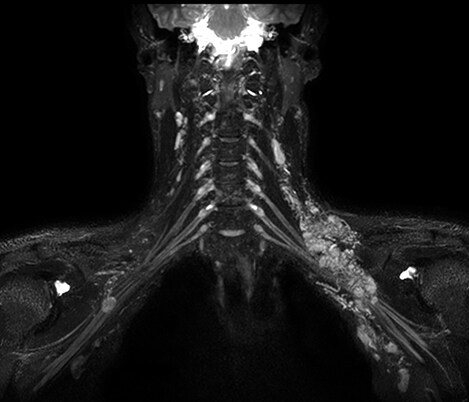

Casos clínicos de casi todas las anatomías Explore más de 100 casos clínicos de sus colegas en todo el mundo que muestran cómo la tecnología digital de resonancia magnética de Philips fortalece sus necesidades de imágenes.